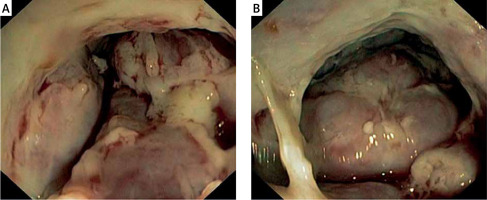

Colonoscopy was performed, revealing tumour-like, whitish, and hard (on biopsies) mass located in the proximal part of the anal canal, rectum, and rectosigmoid junction (Figure 1). Standard histopathology examination was suggestive of immunoproliferative disease, requiring further evaluation. Immunohistochemistry was performed and showed CD38+, κ+, λ–, MUM-1+, EBV-LMP-, CD20-, CD138-, and Ki 67+ in 60% positive cells, indicating plasmablastic plasmacytoma (Figure 2). Further diagnostic algorithm excluded possible differential entities such as myeloma and lymphoma. Serum protein electrophoresis detected paraprotein, and immunofixation identified immunoglobulin G (IgG), λ type. Urine protein electrophoresis did not indicate the presence of Bence-Jones protein. Alkaline phosphatase, calcium level, and lactate dehydrogenase were normal, and the concentration of β2 microglobulin was elevated (13.2 mg/l, reference range: 0.9–3.0 mg/l). Sternal biopsy showed unspecific reactive bone marrow changes without elements of lymphoproliferative disorders. Multislice computed tomography (MSCT) showed a tumour mass 10 × 11 × 16 cm in size occupying the abdomen and pelvis, surrounding the rectum, iun the proximal part of anal canal, with parailiac adenopathy, ascites, and peritoneal involvement, and invading the urinary bladder and prostate (Figure 3). We additionally reviewed slides from previous biopsies, which surprisingly revealed monoclonality despite gross histopathology being normal. His performance status prevented him from receiving further oncological therapy. His condition progressively worsened, and he died 1 month after the diagnosis was established.

Presenting symptoms are usually related to the site of plasma cell infiltration. In our case the patient claimed diarrhoea and blood in stool as well as faecal incontinence for the past 2 months. The endoscopic appearance of EMP arising from the gastrointestinal tract may vary, ranging from small sized polyp, as in the case reported previously by Miwa et al., to ulcerated masses or massive, whitish infiltration (as in the present case). Colonoscopy showed a massive tumour, which could be mistaken for adenocarcinoma or a neuroendocrine tumour (NET). Diagnosis of EMP must be supported by biopsy and immunohistochemistry following the exclusion of other possible diseases.